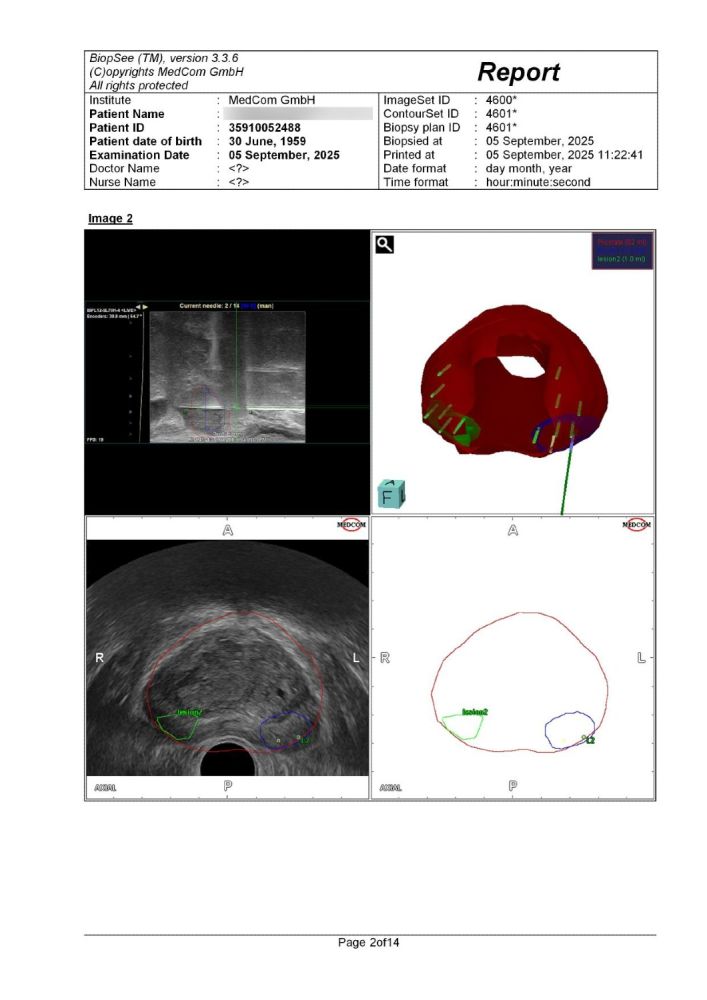

Αναφορά του συστήματος Biopsee όπου φαίνονται οι στοχευμένες βιοψίες στις βλάβες (δε) & (αρ) που μας εδειξη η Πολυπαραμετρικη MRI προστάτη , όπως και κάποιες στοχευμένες άμφω.